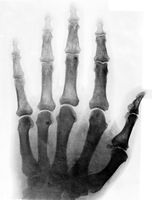

M0019472: X-ray photograph of the left hand of Lord Joseph Lister

Photograph of an x-ray of the left hand of Joseph Lister. At the time the photograph was made, the original was held by King's College Hospital. It is one of a number of photographs accumulated by the Wellcome Historical Medical Museum as part of its exhibition held in 1927 to celebrate the centenary of Lister, in conjunction with The Royal Society, The British Universities Hospitals and Medical and Surgical Colleges.

1 photograph glass plate negative; 12 x 16.5 cm